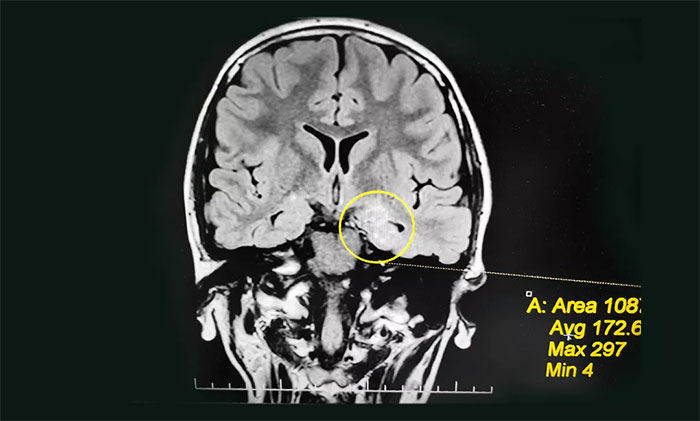

入院后,佳欣接受了一系列检查:行24小时长程脑电图监测,提示异常脑电图;MRI检查,左侧颞叶海马区影像改变,左侧海马神经元受损、局部代谢旺盛,考虑左侧海马区轴内变性病变,考虑致癫灶可能。

为佳欣诊治的杨忠旭教授查看了各项检查报告,详细了解相关病情后,考虑佳欣因难产导致大脑缺血、缺氧,而海马对这种情况的耐受较差,极易造成其内的神经细胞受损,时间长了就会发展成海马硬化。成年后,近一半以上的病人会因此患上顽固性癫痫。

▲ 通过系列检查评估,最终明确患者致癫灶